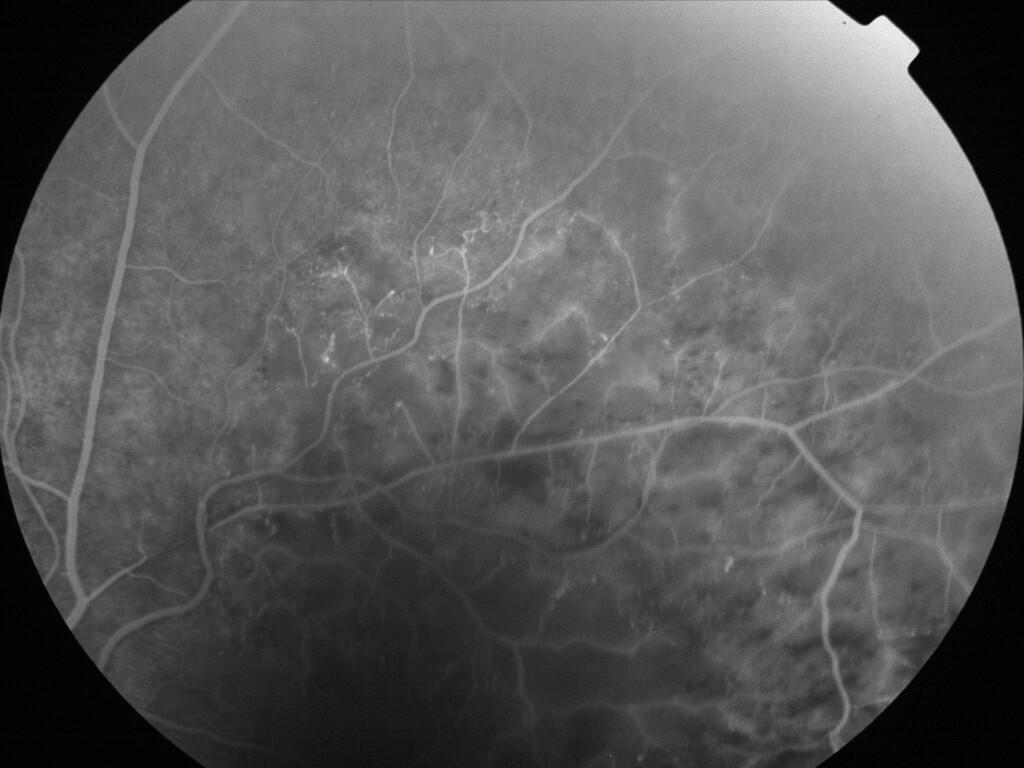

OCCLUSION DE BRANCHE DE LA VTS DE FORME ISCHEMIQUE MAJEURE